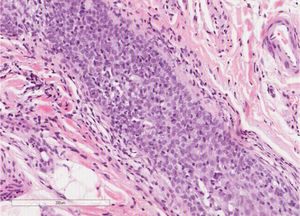

Um homem saudável de 65 anos apresentou história de seis meses de lesões cutâneas generalizadas, alopecia e prurido intenso. No exame dermatológico, foram observadas inúmeras pápulas foliculares pontiagudas e alopecia do couro cabeludo (fig. 1), com lesões queratóticas foliculares na tricoscopia. Alopecia irregular dos pelos do corpo e múltiplas espículas hiperqueratóticas milimétricas no tronco e membros estavam presentes, dando a sensação de pele áspera à palpação. Além disso, observou‐se LSHS na área axilar. Não foi observada linfadenopatia palpável ou visceromegalia. A biópsia do couro cabeludo evidenciou infiltrado de linfócitos atípicos no epitélio folicular, com epidermotropismo (fig. 2). Imuno‐histoquimicamente, os linfócitos foliculares apresentaram positividade para CD3 e CD4, com perda parcial de CD7; CD30 foi negativo. A análise molecular do TCR demonstrou uma população monoclonal de linfócitos. Os exames laboratoriais estavam dentro dos limites normais (hemograma, células de Sézary, bioquímica, eletroforese, imunoglobulinas, β‐2 microglobulina) e nenhum comprometimento sistêmico foi detectado no exame de imagem corporal. Foi estabelecido o diagnóstico de MFF. O paciente foi tratado com interferon alfa (3.000.000 unidades, três vezes por semana) e clobetasol tópico, alcançando remissão completa um ano depois, sem recidivas após três anos de acompanhamento (fig. 3).

A formação de diferentes lesões foliculares na MFF provavelmente é resultado da extensão e do grau de infiltração do folículo piloso pelo infiltrado neoplásico. A presença de linfócitos atípicos, especialmente quando formam coleções no epitélio folicular, é a principal característica para o diagnóstico. No entanto, o infiltrado pode conter outras células inflamatórias e a atipia nuclear pode ser de pequeno grau, dificulta o diagnóstico. Além disso, as características histopatológicas das lesões foliculares hiperqueratóticas, como lesões similares à queratose pilar (LSQP) e MFF com espículas, podem ser sutis, com infiltrado foliculotrópico de baixa densidade, sugestivo de MFF precoce. Além disso, na MFF com espículas pode ser observada uma coluna ortoqueratótica ou paraqueratótica que sobressai da obstrução folicular; também é notável a ausência de células inflamatórias associadas e mucinose folicular.3 Os linfócitos foliculotrópicos são geralmente CD4+(e frequentemente CD7−) e menos comumente CD8+, com ocasional rearranjo de genes gama de receptores de células T.